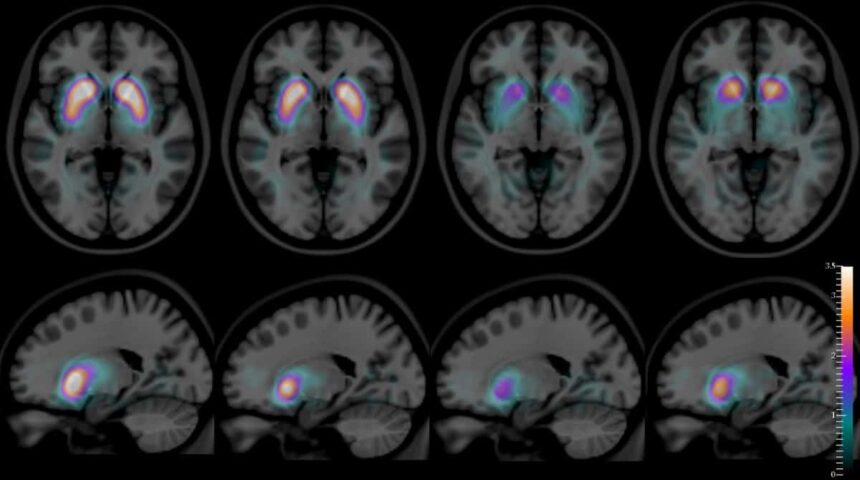

Pituitary Adenoma

Located in the middle of the brain, this tiny organ works like an orchestra conductor that controls all the glands in your body. Your doctor may request a pituitary MRI after some abnormalities in the blood tests to evaluate the functions of...